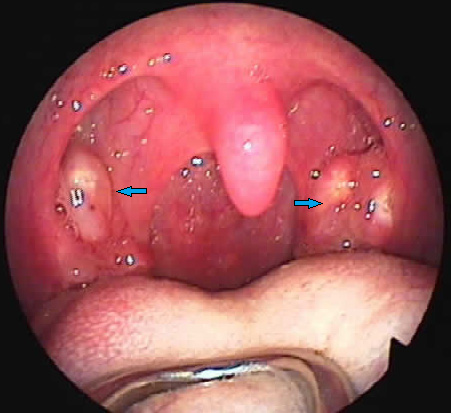

Yết hầu thũng thống là hiện tượng yết hầu sưng đau, lúc đầu có thể thấy ngứa họng, thích khạc nhổ, kèm theo sốt hoặc tiết nhiều đờm dãi. Nếu nặng không chữa kịp thời, yết hầu nghẹn đau, ăn uống khó khăn, họng sưng đỏ lưỡi gà đỏ, nuốt nước bọt cũng đau, lưỡi đỏ hoặc hồng nhợt. Dưới đây, chúng tôi xin giới thiệu các phương thuốc điều trị tuỳ từng thể bệnh:

Lưỡi gà, họng sưng nề.